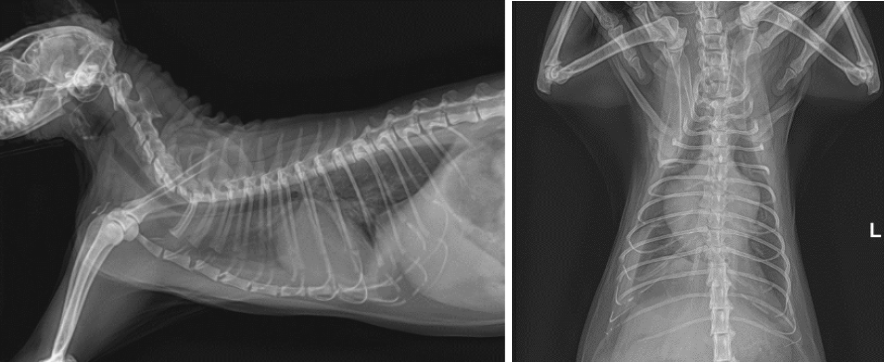

01 흉부 방사선 검사

흉부 방사선 촬영상 심각한 수준의 심장비대와 폐수종, 흉수, 심낭수 소견이 확인되었습니다.

양산 고양이 심장병 RCM 흉부 방사선 검사 결과 / 출처: 에스동물메디컬센터 양산점